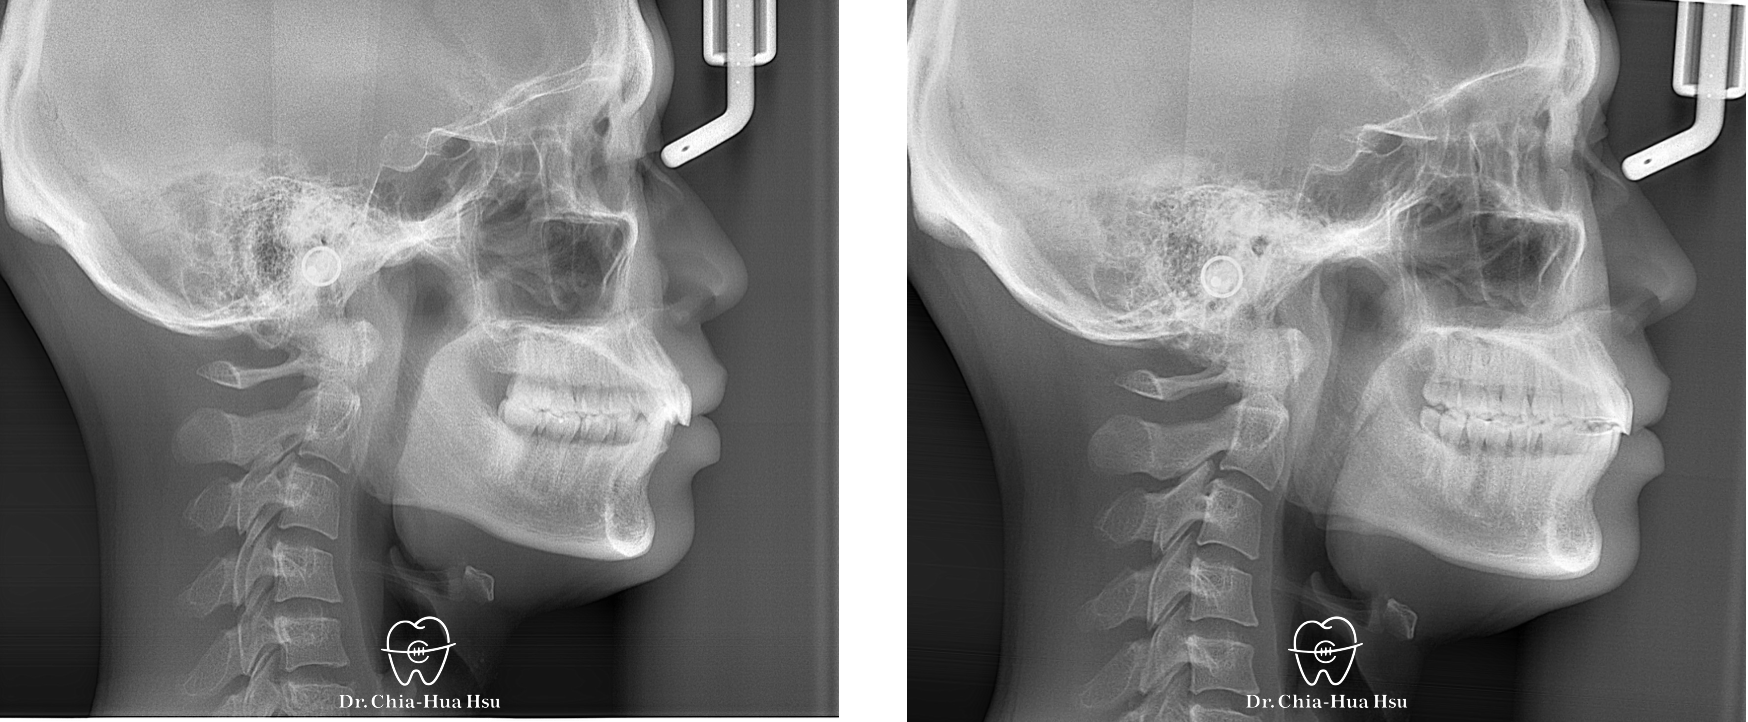

治療前

治療後

治療前

治療後